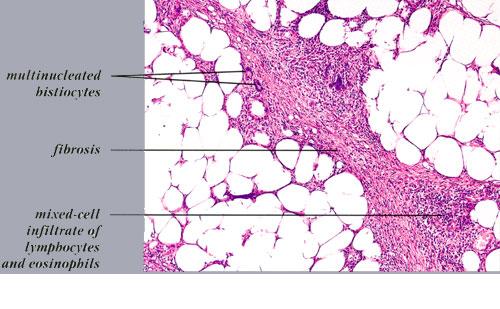

Histopathology. The histologic changes are present mainly in and near the septa of the subcutaneous tissue .

. The overlying dermis often has only a minimal to moderate, superficial and deep perivascular lymphocytic infiltrate.

In the early lesions of acute erythema nodosum, there is edema of the septa with a Iymphohistiocytic infiltrate, having a slight admixture of neutrophils and eosinophils . Focal fibrin deposition and extravasation of erythrocytes occur frequently  and can be revealed by spectral microscopy . Often, the inflammation is most intense at the periphery of the edematous septa and extends

into the periphery of the fat lobules between the individual fat cells in a lacelike fashion. Necrosis of the fat is not prominent. Rarely, clusters of neutrophils are present or the infiltrate is predominantly neutrophilic . Clusters of macrophages around small blood vessels, or a slitlike space, occur in early lesions and are known as Miescher's radial nodules . Some authors have failed to find central vessels  and have considered Miescher's nodules to be characteristic of erythema nodosum, stating that they can be found in all stages of erythema nodosum . The degree of vascular involvement is variable . Usually, there is edema of the walls of veins with separation of the muscular layers . Infiltration by lymphocytes is common, but neutrophils and eosinophils can be present as well. Necrosis of the vessel walls is very rare but has been observed in a few patients with lesions clinically indistinguishable from erythema nodosum . For example, focal vasculitis has been found in a few patients with acute erythema nodosum secondary to infections  and in a few cases of recurrent

Later lesions of acute erythema nodosum show widening of the septa, often with fibrosis and with inflammation at the edges of the septa and involving the periphery of the fat lobules . Neutrophils usually are absent, and the vascular changes are less prominent than in early lesions. There are more macrophages in the infiltrate. Macrophages at the edges of the fat lobules show phagocytosis of lipid from damaged adipocytes, and the small droplets of lipid in their cytoplasm give them a "foam cell" appearance. Granulomas formed by macrophages, without lipid deposition, are more frequent

when late lesions are compared with early ones . The granulomas often are loosely formed with macrophages predominating in a focus with multinucleated giant cells. Occasionally, well-formed, discrete sarcoidal granulomas occur in small numbers in the septa. The multinucleated cells usually have an irregular distribution of the nuclei in the cytoplasm. The oldest lesions have septal widening and fibrosis with a decrease in all of the inflammatory cells.